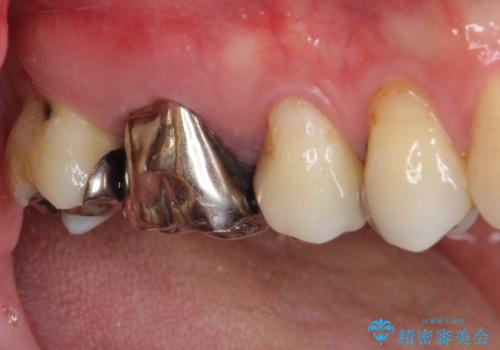

- 奥歯に強い痛みを感じるとのことで来院された患者様です。

診査したところ、既に根管治療されている大臼歯の咬合痛と、神経の残っている手前の小臼歯の強い冷熱痛を認めました。

神経の残っている小臼歯は神経を取り除く必要があったため、速やかに根管治療を行うこととしました。

隣に位置する既に根管治療されている大臼歯は、手前の小臼歯の痛みが波及している可能性も考えられたため、小臼歯の根管治療後に改めて診査をした上で治療方針を定めることとしました。